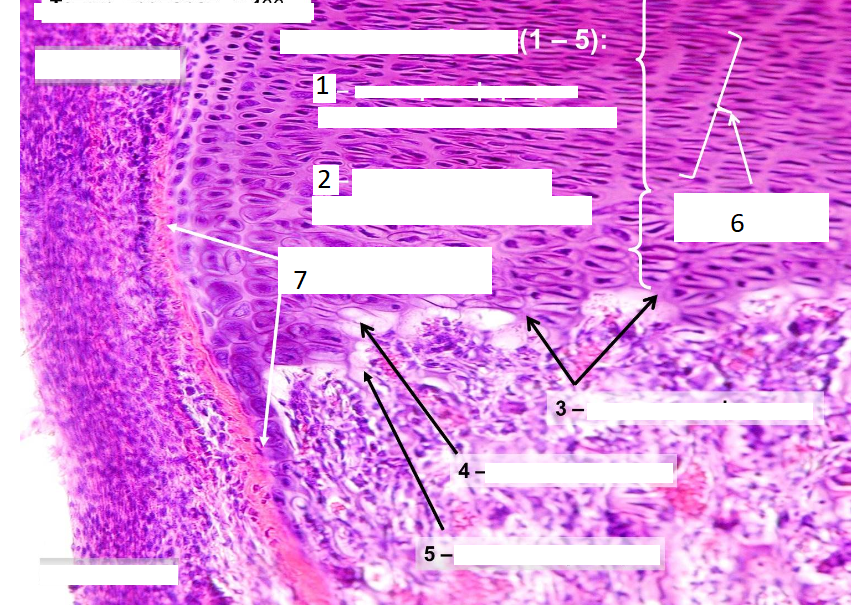

Препарат: Образование кости на месте гиалинового хряща (непрямой остеогистогенез)

1. Зона пролиферации (зона монетных столбиков)

2. Зона гипертрофии (зоны пузырчатого хряща)

3. Зона кальцификации

4. Эрозионная зона

5. Зона оссификации

6. Колонка хондроцитов

7. Перихондриальная костная манжетка

8. (1-5)-это зоны метафиза

Слева сверху надхрящница, она покрывает хрящ, благодаря ей осуществляется питание хряща, она содержит кровеносные сосуды, нервы, камбиальные элементы.

Слева снизу надкостница, через которую проникают сосуды в Фолькмановы пространства, она покрывает кость снаружи.

Непрямой остеогистогенез происходит на основе гиалиновой хрящевой ткани, лежит в основе регенерации кости, развитие большинства костей скелета.